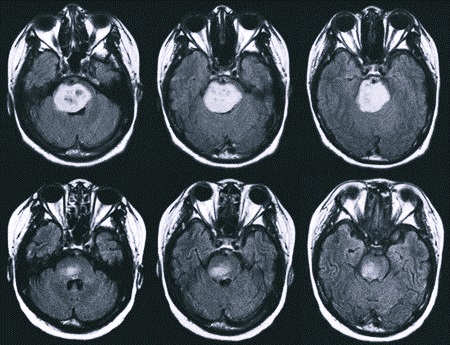

При возникновении таких симптомов нужно обратиться к врачу. Больному будет назначено проведение МРТ, что позволит определить наличие опухоли.

Прогноз всегда зависит от того, какая именно опухоль у больного. Большое значение имеют темпы ее роста, размер и точное расположение. Доброкачественные новообразования легко удаляются хирургическим путем, для чего делается разрез, через который иссекается сама опухоль. Злокачественные же убрать таким методом не получится, поэтому придется отдать предпочтение лучевой терапии или другим методикам.